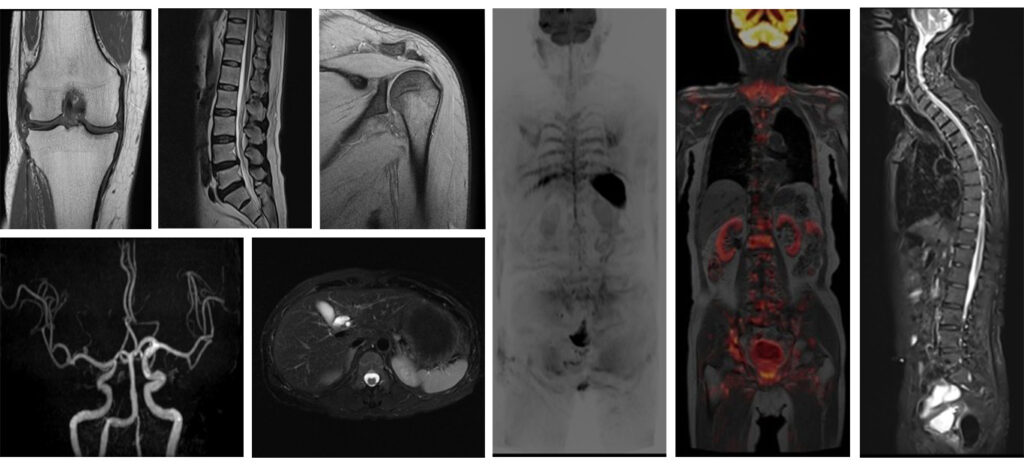

MRI検査室

超電導磁石が埋め込まれたトンネルに体を入れ磁石と電磁波によって体の中の情報を解析し画像にします。いろいろな角度から体の断面を画像化することができ、脳、脊髄、臓器、筋肉、関節、血管などの情報を得ることができます。また、X線を使わないため被ばくの心配がありませんが検査中は大きな音がします。